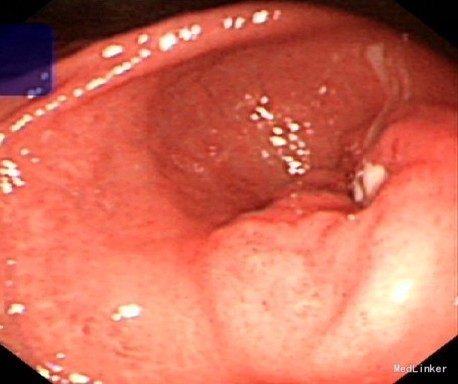

诊断考虑胃溃疡并胃窦狭窄并不全梗阻,根据溃疡形态,考虑恶性病变不排除,向患者及家属解释病情,并建议手术治疗,患者仍坚持内科保守治疗及观察,继续予加强抑酸、护胃治疗近2周后复查胃镜(见图3)病情较前无改善,再次多点活检仍未见癌,经反复劝说,患者及家属终于同意行手术治疗。术中见胃窦幽门管处环形狭窄,近端胃壁明显水肿增厚,幽门管处与横结肠系膜粘连紧密,难以剥离,胃窦环形狭窄处取活检示:低分化腺癌,探查明确胃窦癌浸润横结肠系膜及胰头部,其中横结肠系膜及胰腺成团块状,难以分离切除,遂行姑息性远端胃切除,十二指肠断端包埋不理想,遂行十二指肠残端造瘘,胃空肠吻合重建消化道。

该病例为老年男性,初次胃镜检查见胃窦溃疡形态符合良性溃疡特点,病理活检未见癌,但因患者未及时复查,3月后复查胃镜见溃疡进展并出现了胃窦狭窄并不全梗阻,多次活检仍未见癌,但手术后明确胃窦腺癌诊断,且病情严重,已无法完全分离切除。通过该病例我们可以得出以下经验及教训:1.胃溃疡病人治疗后的胃镜复查是必要的,特别是对于一些高危病人,应强调短期治疗后复查胃镜,2.胃镜下活检受很多因素影响,其结果有一定局限性,特别对于像本病例这样的特殊位置的病变,哪怕多次、多点及深挖活检均未能明确诊断,对于高风险病人、治疗效果欠佳、胃镜下形态高度怀疑恶变的病例应当及时予以手术探查,以免贻误病情。